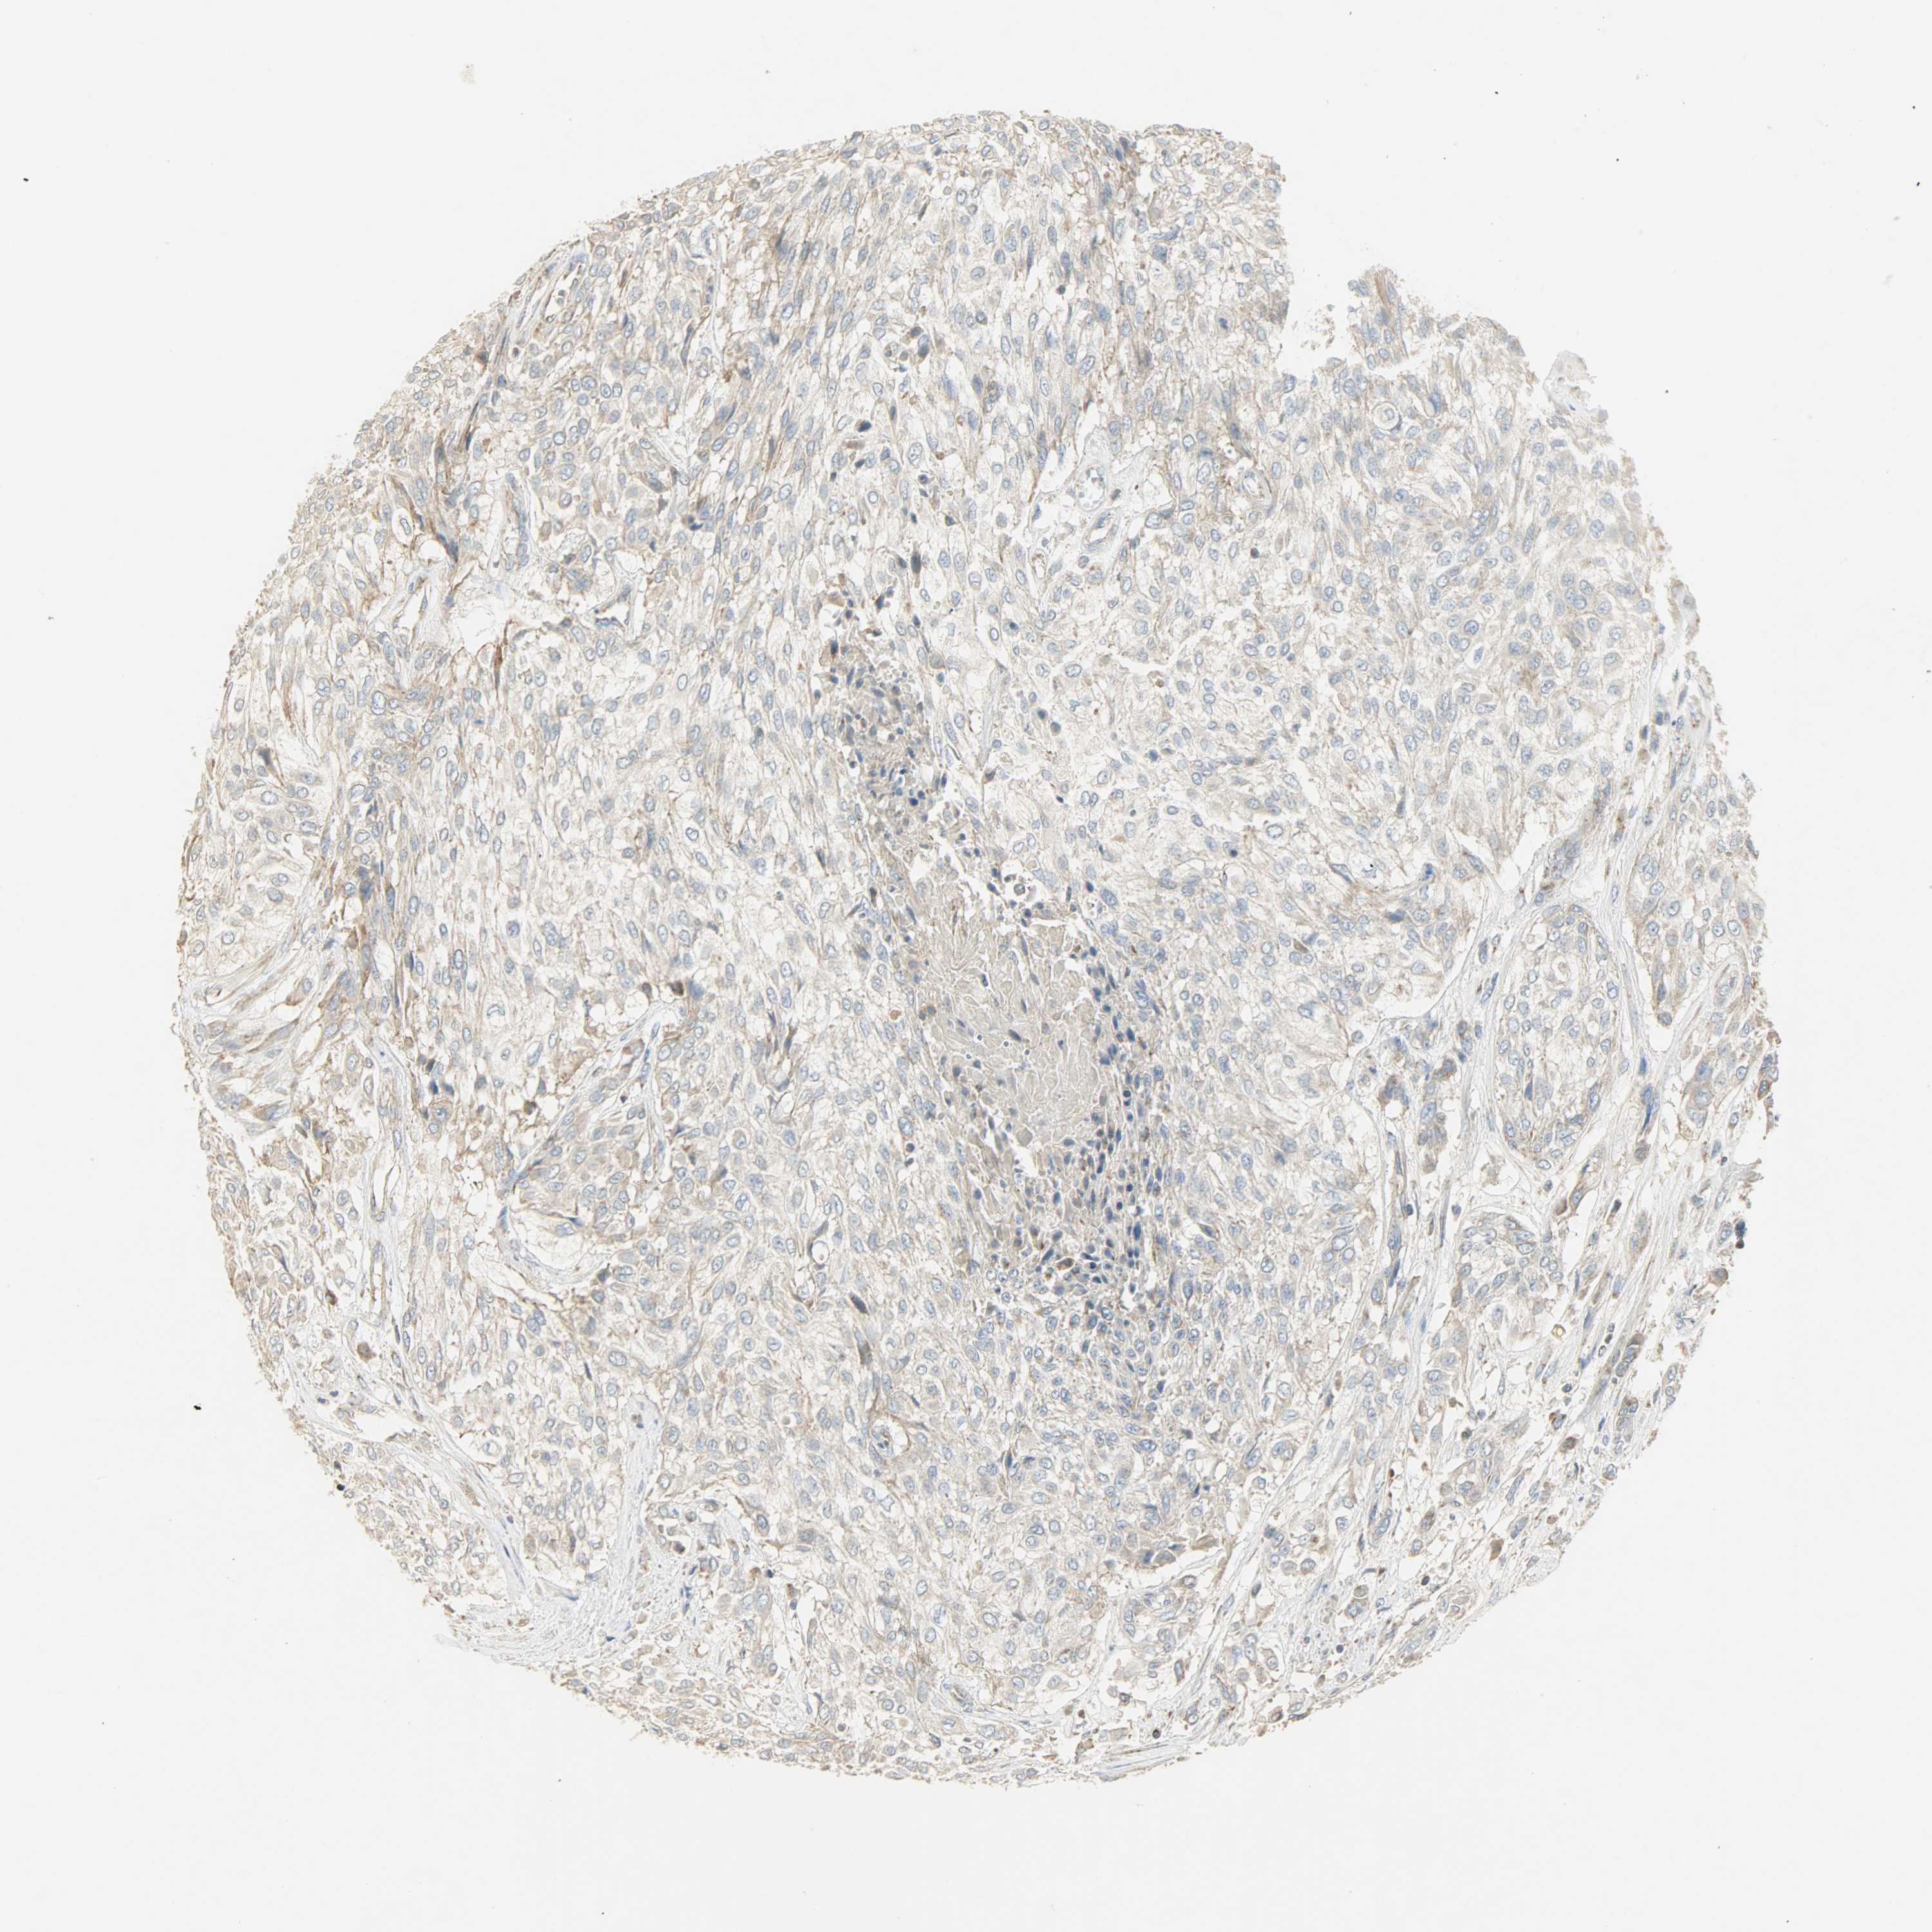

UROTHELIAL CANCER - Protein expressioni

A mouse-over function shows sample information and annotation data. Click on an image to view it in a full screen mode. Samples can be filtered based on level of antibody staining by selecting one or several of the following categories: high, medium, low and not detected. The assay and annotation is described here.

Antibody stainingi

Antibody staining in the annotated cell types in the current human tissue is reported as not detected, low, medium, or high, based on conventional immunohistochemistry profiling in selected tissues. This score is based on the combination of the staining intensity and fraction of stained cells.

Each image is clickable and will lead to virtual microscopy that enables deeper exploration of all samples and also displays staining intensity scores, fraction scores and subcellular localization as well as patient and tissue information for each sample.

Antibody HPA004829

Antibody CAB004975

Urothelial carcinoma, High grade

Urothelial carcinoma, Low grade